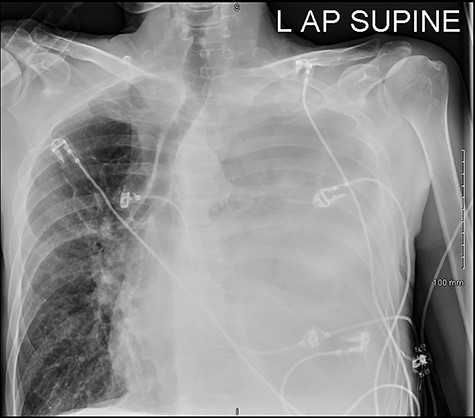

He maintained a high daily chest drain output of between 2.5 and 5 l. Upon recommencement of enteral feeding on day 3, we noticed an increase in opacity of the drainage fluid (Fig. 3). Normal triglyceride and chylomicron levels ruled out a chylothorax. Cultures from the drain eventually grew Enterococcus faecium, Candida albicans and Escherichia coli consistent with gut flora. At this point, an aerodigestive fistula was suspected. This was confirmed by a dye test subsequently performed with green ice cream, which tainted the drainage fluid green (Fig. 4). A repeat CT scan with oral and intravenous contrast delineated a fistula between the greater curvature of the stomach and the left basal pleura, with an extensive empyema (Fig. 5).